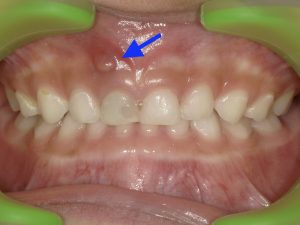

2. 歯茎の「おでき」や「できもの」

歯の根の先に溜まった膿が、歯茎を破って出てくることがあります。これはフィステルやサイナストラクトと呼ばれるもので、ニキビのような白いできものが歯茎にでき、膿が出たり引っ込んだりします。痛みがないことが多いため、見過ごされがちです。